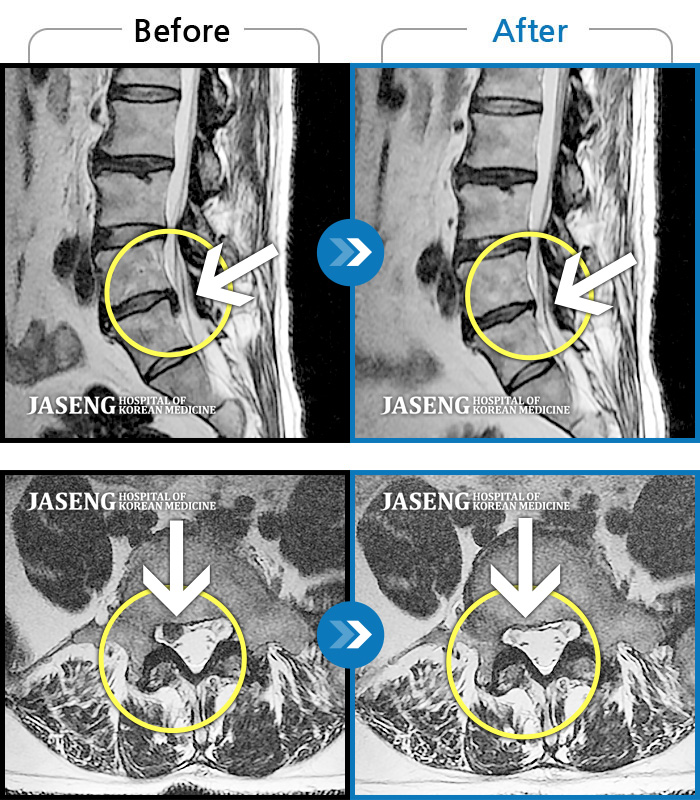

허리통증으로 약 6개월 동안 치료를 받고 이제는 완쾌되어 건강하게 후기를 작성하고 있습니다.

처음에는 극심한 통증으로 병원에 오는 것 조차 어려웠으나, 꾸준한 치료와 약침의 효과 덕분에

1달 이후에는 일상생활에 큰 지장이 없을 정도로 호전되었고, 이후에도 지속적으로 치료를 받음

으로써, 아프기 전의 상태로 되돌아 간 것 같습니다.

매주 일산병원에 방문할때마다 친절하게 증세를 점검해 주시고 치료를 해주신 김태용 원장님,

그리고 담당 간호사 선생님께 감사의 말씀을 드립니다.

제 지인이나 주위 사람중에 허리통증이 있는 사람에게는 적극 추천토록 하겠습니다.